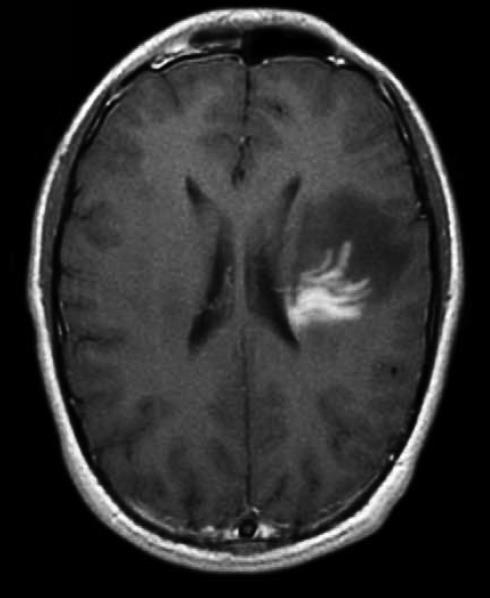

• 肿瘤样脱髓鞘病变报道3例

2023, 48(5):614-617. DOI: 10.13406/j.cnki.cyxb.003183

摘要 (95) HTML (24) PDF 1.29 M (241) 评论 (0) 收藏

摘要: